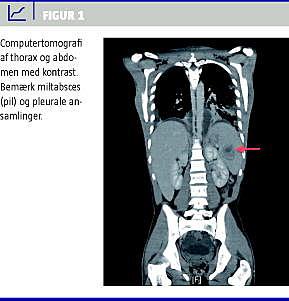

En 16-årig ung mand blev indlagt via en vagtlæge efter seks dages anamnese med halssmerter, abdominalia og svingende febrilia. Før indlæggelsen var patienten blevet fulgt af egen læge, som havde set tilstanden an uden at give antibiotika grundet negativ Strep A-test. Ved indlæggelsen blev der diagnosticeret en peritonsillær absces, som blev dræneret. Grundet svær sepsis og tiltagende respiratorisk påvirkning blev patienten efterfølgende overflyttet til intensiv terapi-afsnit. En computertomografi (CT) af collum, thorax og abdomen viste restabscesser i tonsillejet, pleuraempyem, flere lungeabscesser og en enkelt miltabsces (Figur 1 ). Der blev foretaget pleuracentese og tonsillektomi og påbegyndt bredspektret antibiotisk behandling med piperacillin/tazobactam, metronidazol, ciprofloxacin og gentamicin. Ved bloddyrkning blev der fundet vækst af FN, hvilket er foreneligt med Lemierres syndrom.